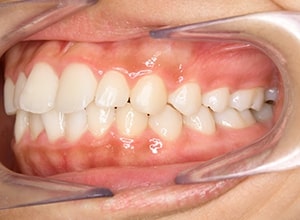

| 口腔内所見 | over jet 3.5mm,over bite4.0mm、下顎正中右側偏位2.0mm、大臼歯関係は左側Ⅰ級であったが、右下6は右下E早期喪失のため近心傾斜しておりⅢ級の臼歯関係となっていた。また上下顎前歯は軽度の叢生を呈していた。 |

| 批評・予后 | 右下5及び7の萌出前に右下6を整直させることによって、右下5の自然萌出が可能となり正常咬合への咬合誘導が行えたと思う。 |